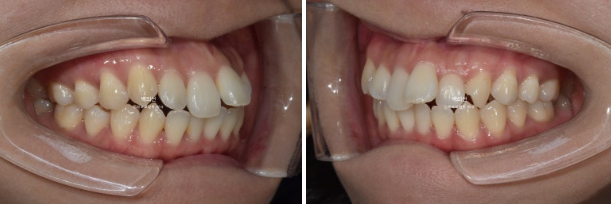

23년 1월 교정을 위해 내원한 30대 환자분입니다.

고치고 싶은 것은 돌출입이였고 장치는 인비절라인 선택하셨습니다.

앞니 덧니가 보입니다.

중심선이 약 2mm 어긋나 있습니다.

앞니 뻗침은 심한 편 입니다.

인비절라인을 원하셔서 인비절라인 발치교정을 권유드렸습니다.

작은어금니 4개를 발치하기로 했습니다.